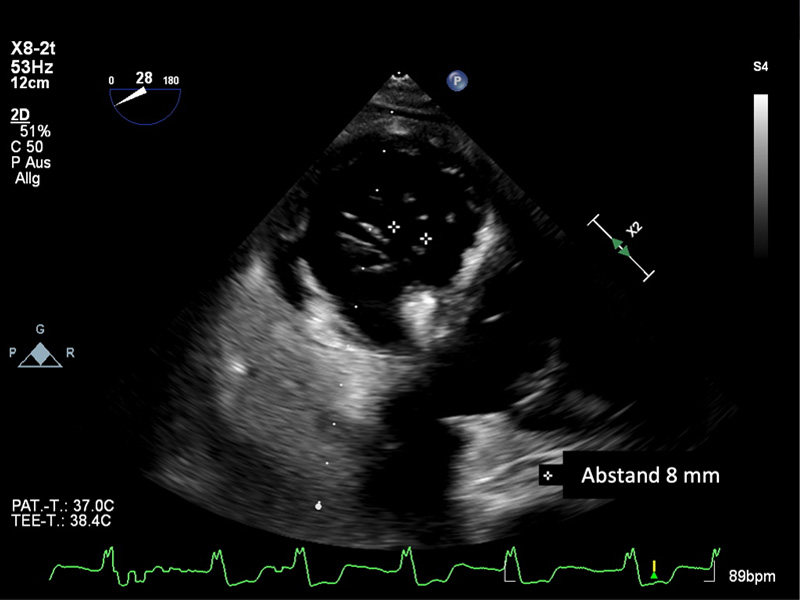

Der Koaptationsdefekt wurde durch den Annuloplastie-Effekt des 1.TriClips auf 8mm reduziert

Transgastrischer Blick auf den zentralen Koaptationsdefekt nach Implantation von 2 TriClip XTW in die anteroseptale Region.

Eine weitere Verringerung des zentralen Koaptationsdefektes auf 5mm ist zu erkennen.